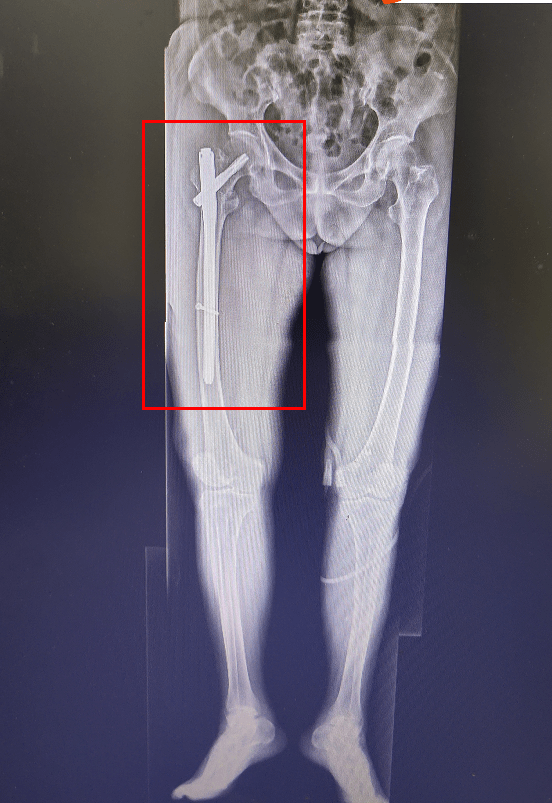

左侧股骨转子间骨折

手术技巧:股骨转子间骨折髓内钉内固定术(视频)

股骨转子间骨折(股骨粗隆间骨折)

近日我科成功为一高龄股骨转子间骨折患者实施手术